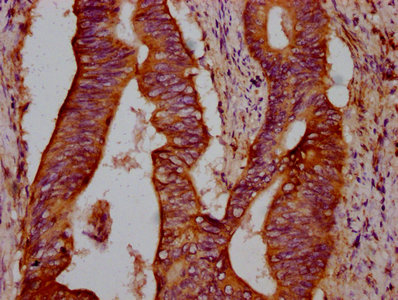

IHC image of CSB-PA615690LA01HU diluted at 1:300 and staining in paraffin-embedded human lung tissue performed on a Leica BondTM system. After dewaxing and hydration, antigen retrieval was mediated by high pressure in a citrate buffer (pH 6.0). Section was blocked with 10% normal goat serum 30min at RT. Then primary antibody (1% BSA) was incubated at 4°C overnight. The primary is detected by a biotinylated secondary antibody and visualized using an HRP conjugated SP system.